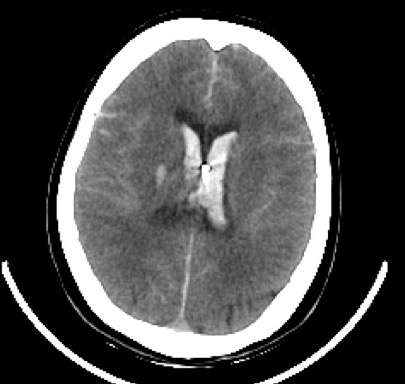

最後まで患者と向き合い、透明性の高い医療を行う。千葉大学医学部附属病院放射線科はその目標のもと、死後画像所見の蓄積とその解析に力を注いでいます。突然の死亡事例の死因究明の一助として、画像診断の役割は年々高まりつつあります。くも膜下出血(下図)や大動脈解離などの死亡原因がCTを撮影することにより明らかになっています。